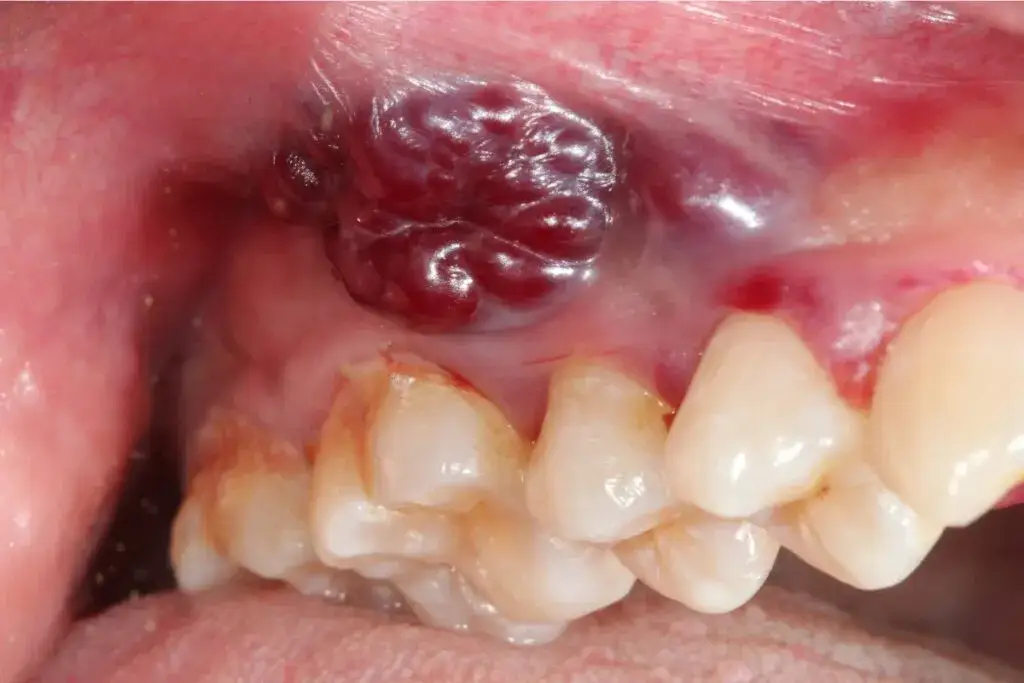

Rozpoznaj wczesne objawy raka jamy ustnej na zdjęciach: leukoplakia, owrzodzenia, guzki. Poznaj czynniki ryzyka i sprawdź, jak postępować. Działaj szybko!